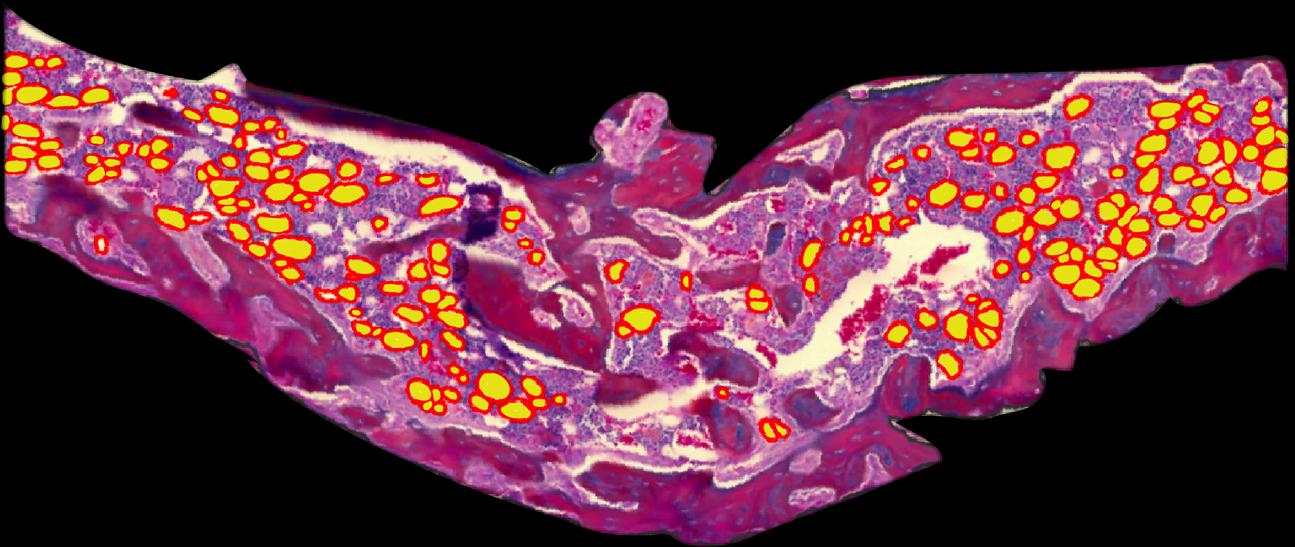

Honey Hendesi | Soft Intruders

2024 Art In Science Submission | Other Scientific

Adipocytes accumulation within Fracture Callus of an obese mouse are indicating reduced osteoblast and new bone formation